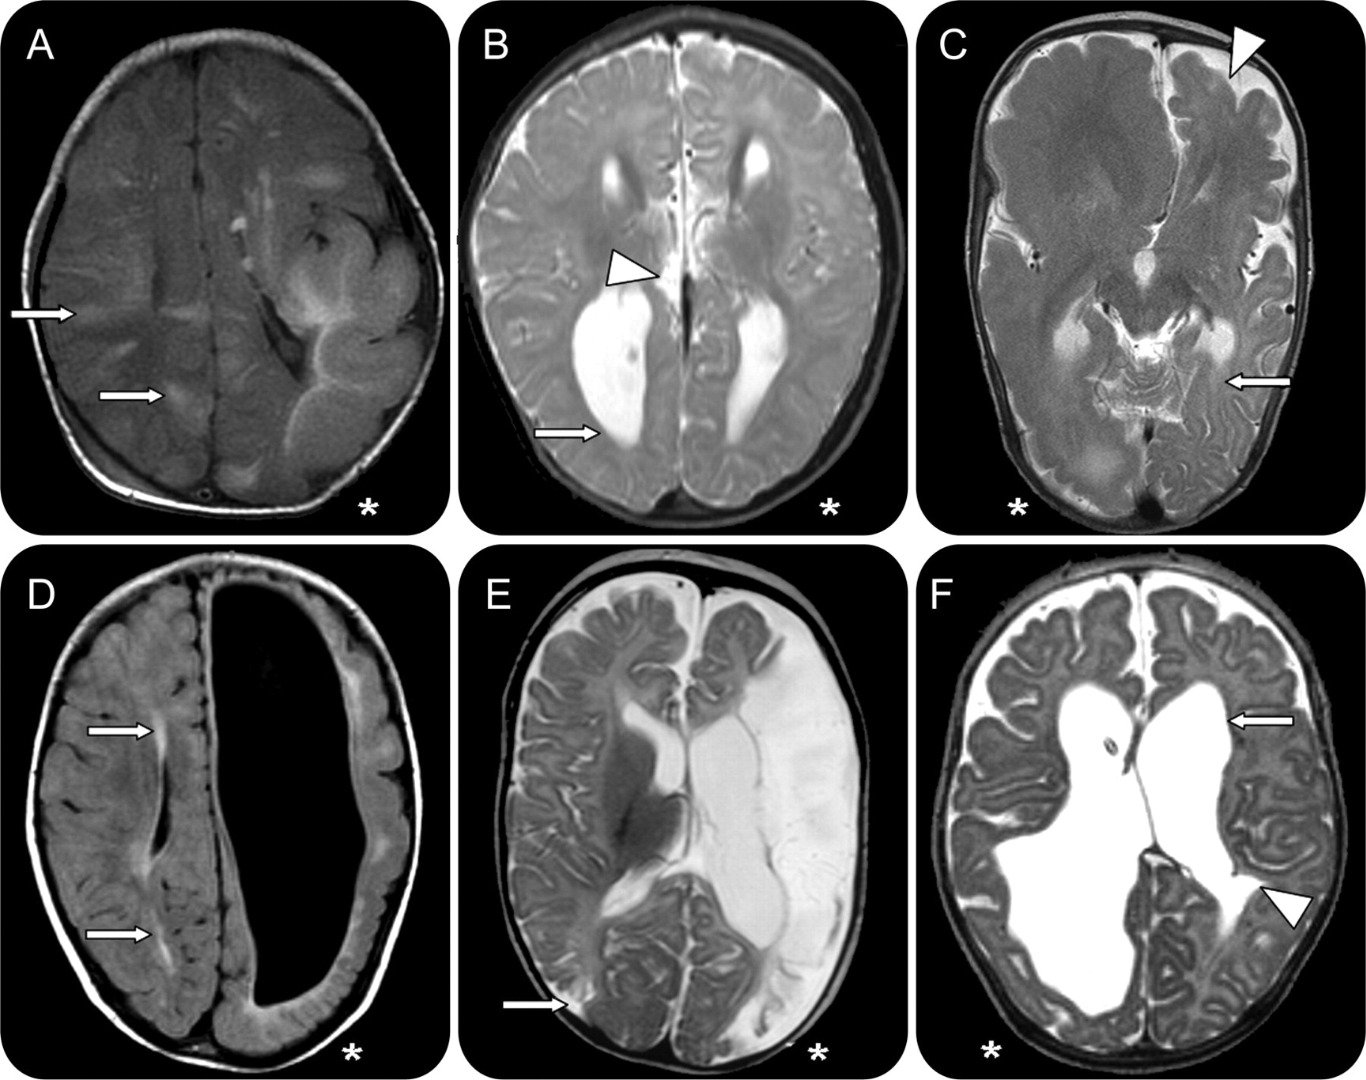

استئصال نصف المخ

عملية استئصال نصف الكرة المخية هي عملية نادرة جدا، وهي تستخدم لعلاج حالات الصرع الحادة جدا، التي تفشل طرق العلاج التقليدية في علاجها، بالطبع مع هكذا عملية قد تحدث عواقب خطيرة مثل الشلل النصفي واعتلال الرؤية، في بعض الحالات يقوم نصف المخ المتبقي بإنماء خلايا عصبية جديدة تحل مكان الخلايا العصبية للنصف المستأصل وتقوم بنفس وظائفها .